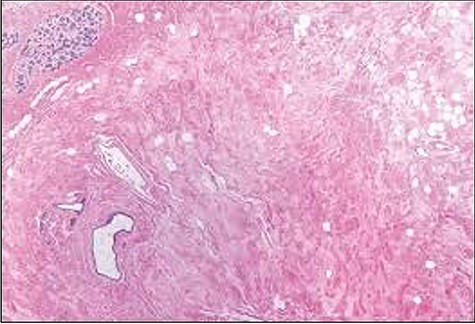

Histological slide showing moderately oedematous interlobular stroma surrounding a normal lobule with lymphangiectasia.

The patient had an uncomplicated recovery period. Histopathological examination of the specimens concluded bilateral GG with lymphangiectasia (Fig. 5). She was counselled on, but declined delayed breast reconstruction, as she was symptom free and otherwise satisfied with the outcome (about 2 months post-surgery) (Fig. 4). Her infant had no significant milestone delays after a short admission period in the special care nursery.